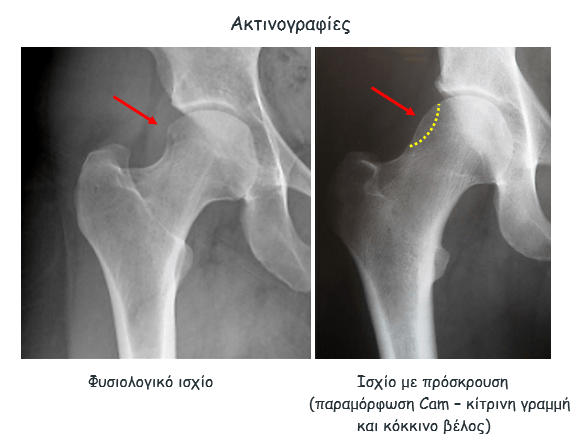

Απεικονιστικές σχολές συνδρομου μηροκοτυλιαίας διακρουσης

Η πάθηση επιβεβαιώνεται με απεικονιστικό έλεγχο. Αυτός περιλαμβάνει:

- ακτινογραφίες,